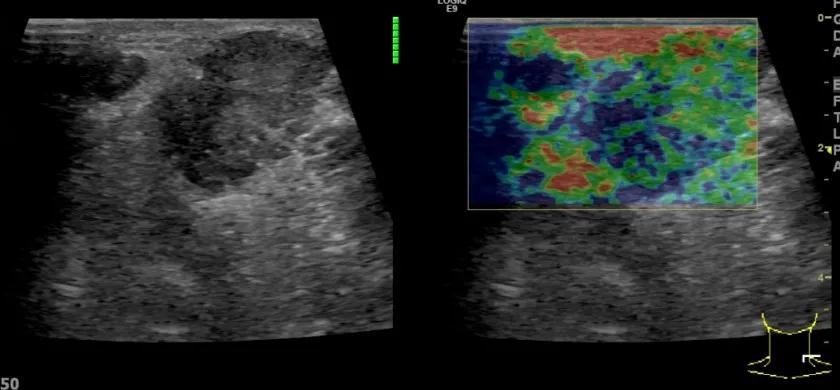

第二例是食管癌患者,术后半年余锁骨上固定淋巴结可触及肿大,疼痛非常明显,系统治疗后无缓解,患者希望通过局部处理缓解症状。造影显示强化信号明显,结节部分区域坏死,故主要针对强化区域从后向前的逐层的消融,皮下进行液体隔离减少烫伤。热消融后影像显示血流增强消失,弹性、硬度增高,一个月后复查显示充盈缺损,完全消融,疗效远超预期。

(病例2图例)